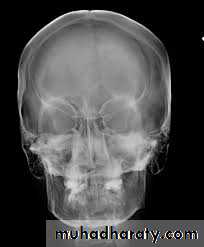

B. Extra oral (Postero-anterior "PA", Anteroposterior "AP", Cephalometric(true lateral), Oblique Lateral, Ocipito-mental, OPG, Submentovertex, TMJ View,etc.).